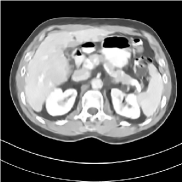

Fig. 3 illustrates the image evolution over SUPER layers (i.e., with evolving network weights in the iterative reconstruction process) for one test case, when using SUPER-WRN-ULTRA. It is apparent that in the early SUPER layers, the proposed SUPER-WRN-ULTRA method mainly removes noise and artifacts, while later SUPER layers mainly reconstruct details such as the bone structures shown in the zoom-in box. A similar behaviour is observed with FBPConvNet-based SUPER methods, which are shown in the supplement (Figs. 13 and 14).

Refer to caption Refer to caption Layer 1RMSE =27.44 HURefer to caption Refer to caption Layer 5RMSE = 26.03 HU

Refer to caption Refer to caption Layer 11RMSE = 25.91HURefer to caption Refer to caption Reference

Figure 3: Image evolution over SUPER layers using the SUPER-WRN-ULTRA method. RMSE values are also indicated.